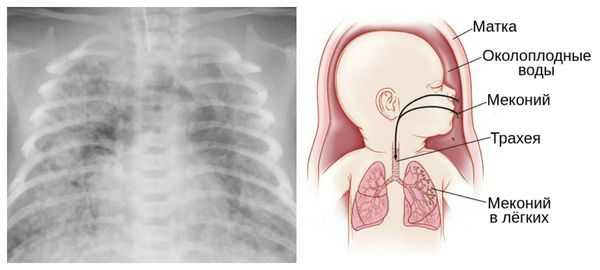

Из-за снижения кровотока в почках плода выделение мочи значительно уменьшается, развивается маловодие. Также изменяется характер околоплодных вод: они теряют прозрачность, становятся мутными, приобретают желтоватый или зеленоватый оттенок из-за примеси мекония — первых фекалий ребёнка.

За счёт изменения состава околоплодных вод нарушается выработка сурфактанта — вещества, которое не даёт альвеолам слипаться во время выдоха. Это вызывает патологию лёгочной ткани и нарушение дыхания после рождения. Также снижается защитная функция лёгких: в водах увеличивается число бактерий, что повышает риск инфицирования лёгочной ткани [1] [8] [11] .

Для плода большую опасность представляет асфиксия (острая гипоксия) и отслойка плаценты. Нехватка кислорода внутри утробы стимулирует плод выполнить несвоевременные дыхательных движения. Они приводят к заглатыванию вод и возможному воспалению лёгочной ткани — пневмониту. Если в водах есть примесь мекония (первородного кала), то велика вероятность мекониальной аспирации — проникновения содержимого кишечника новорождённого в его лёгкие.

Опасности переношенной беременности для ребенка заключаются в возможной гипоксии плода и асфиксии новорожденного, развитии поражений головного мозга, получении родовых травм, аспирации мекония и околоплодных вод. Состояние детей, родившихся от переношенной беременности, отягощается выраженной желтухой, гормональными кризами, инфекционными поражениями кожи, неврологическими нарушениями. Впоследствии они нередко отстают от нормального физического и психического развития.